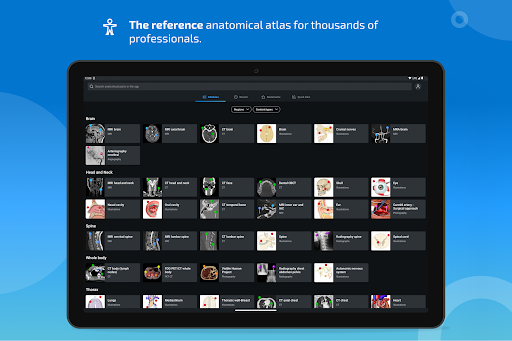

New : You can now filter the modules by region or by content type so you can find the module you are looking for much faster.